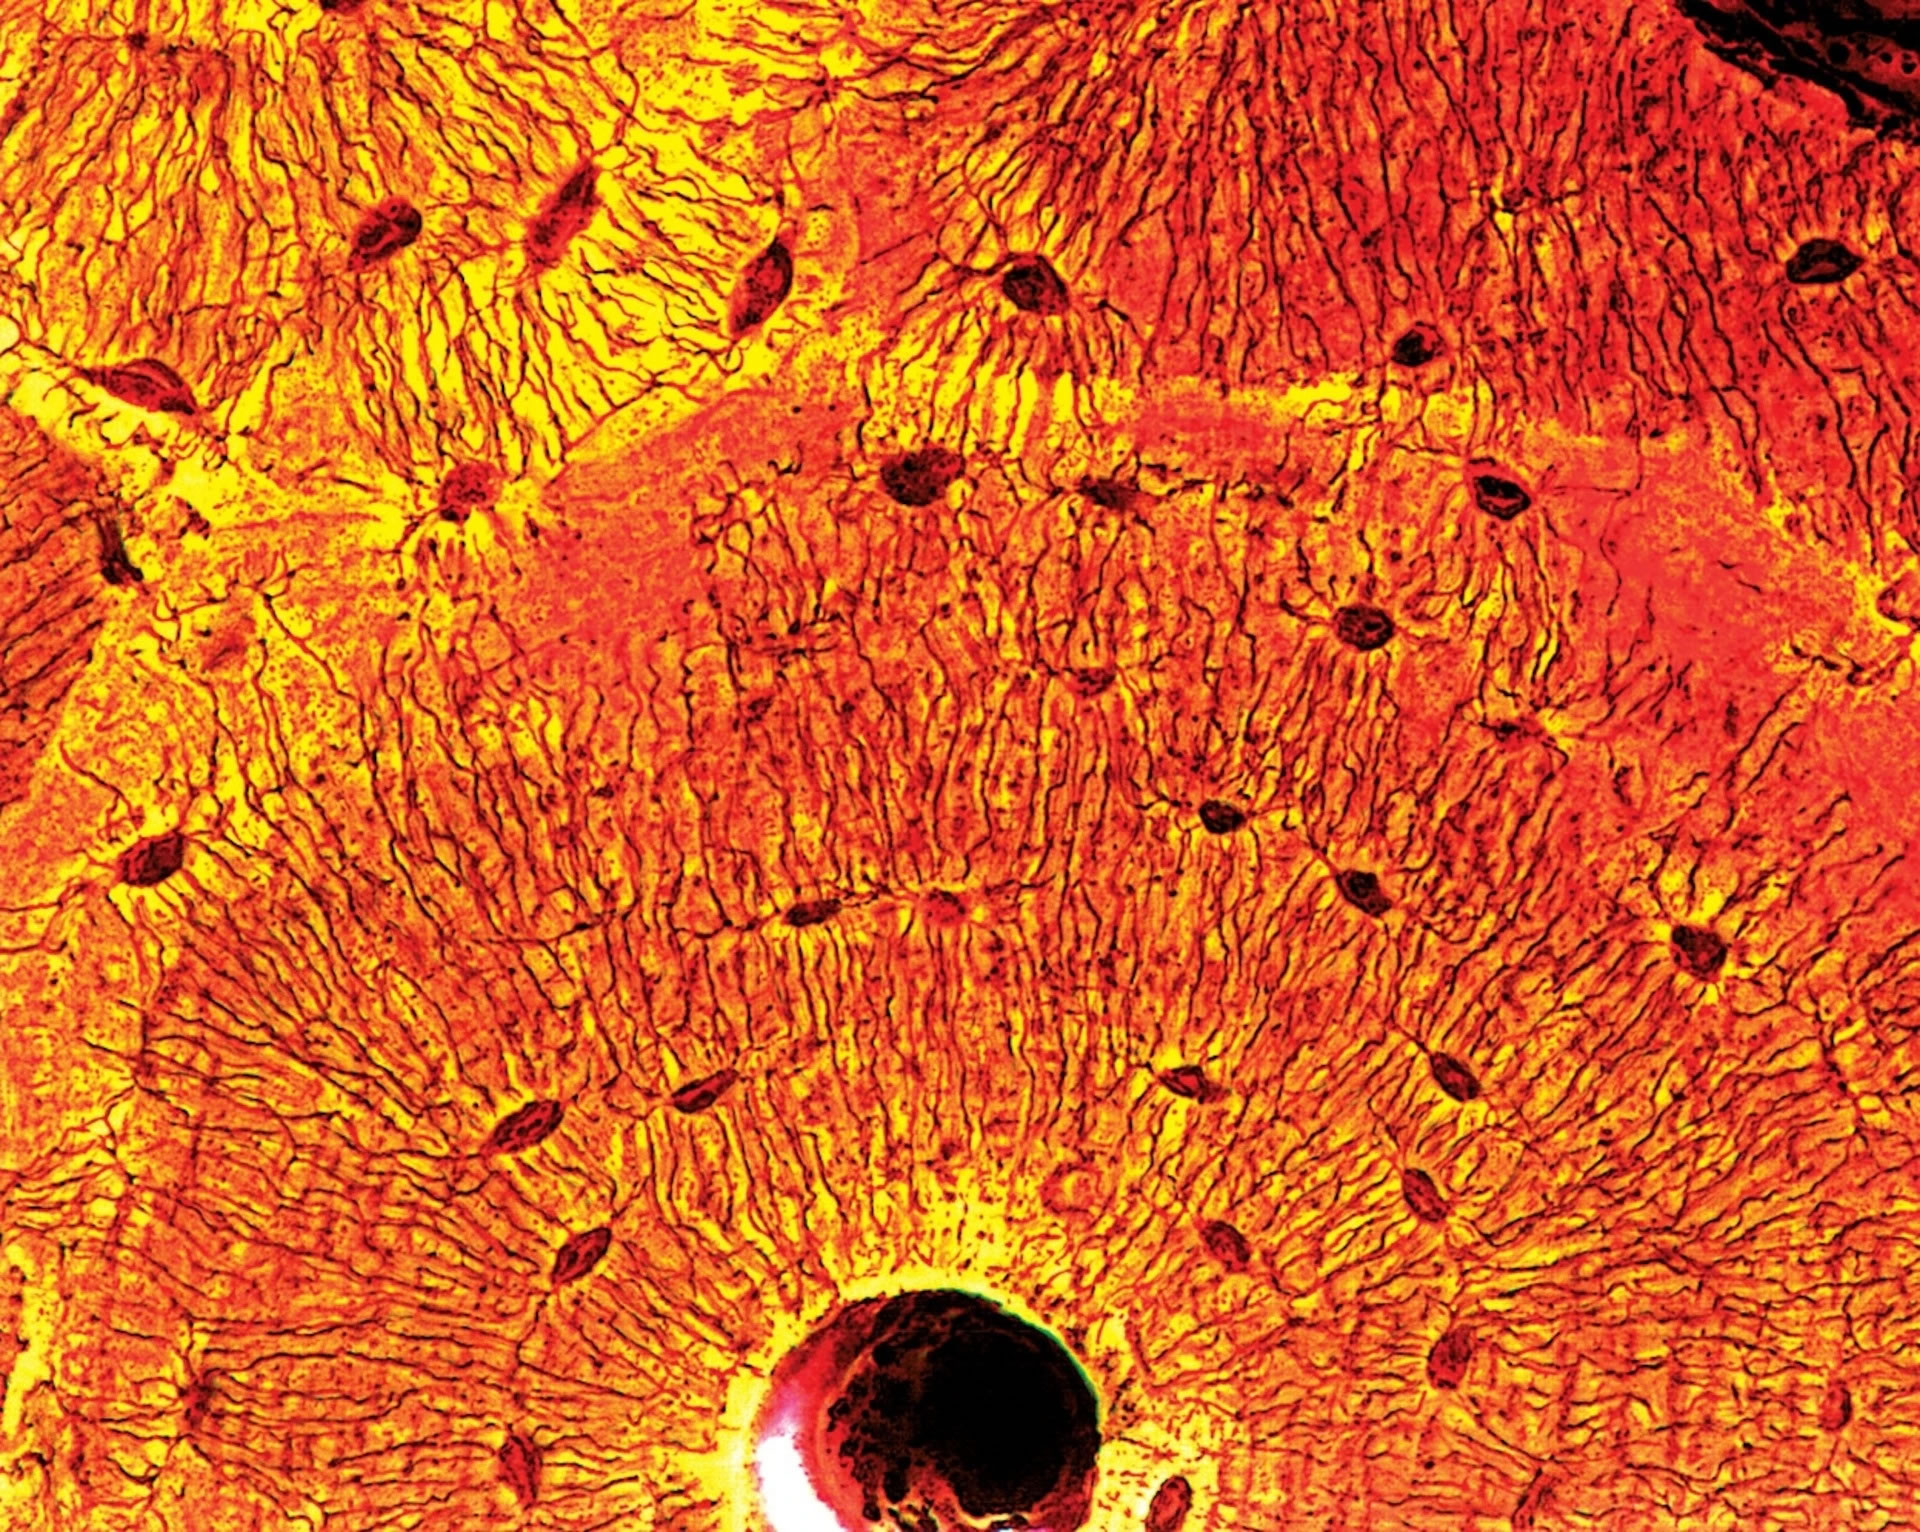

穿透式电子显微镜下的健康心肌。STEVE GSCHMEISSNER / SCIENCE PHOTO LIBRARY

在这幅放大的致密骨(compact bone)断面图像中,骨细胞(黑点)──跟骨重塑(bone remodeling)有关的细胞──会往外分枝、连接其他细胞。PHOTOGRAPH BY QUEST,SCIENCE SOURCE